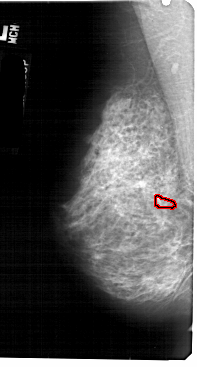

A_1883_1.LEFT_MLO

LEFT_MLO LINES 5491 PIXELS_PER_LINE 2941 BITS_PER_PIXEL 12 RESOLUTION 43.5 OVERLAY

FILE: A_1883_1.LEFT_MLO.OVERLAY

TOTAL_ABNORMALITIES 1

ABNORMALITY 1

LESION_TYPE CALCIFICATION TYPE PLEOMORPHIC DISTRIBUTION CLUSTERED

ASSESSMENT 4

SUBTLETY 1

PATHOLOGY BENIGN

TOTAL_OUTLINES 1

BOUNDARY